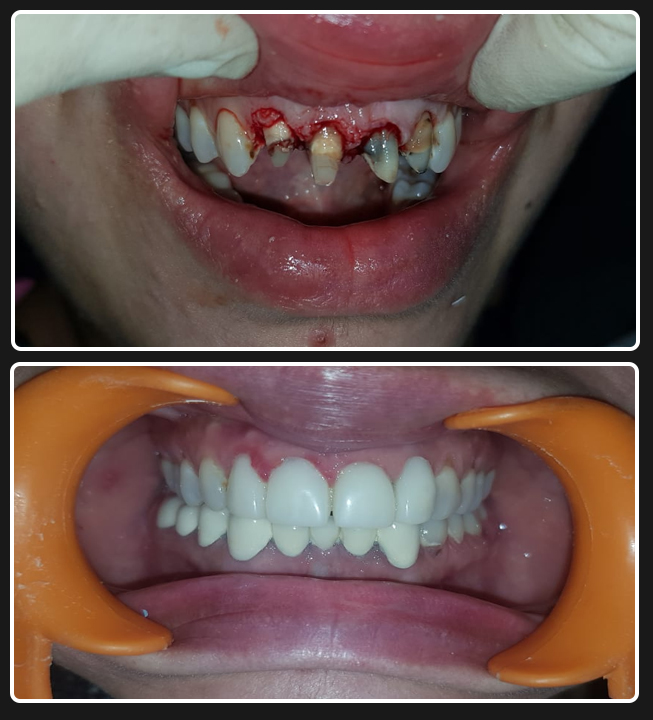

Full Mouth Zirconia (All-Ceramics)

Case 1